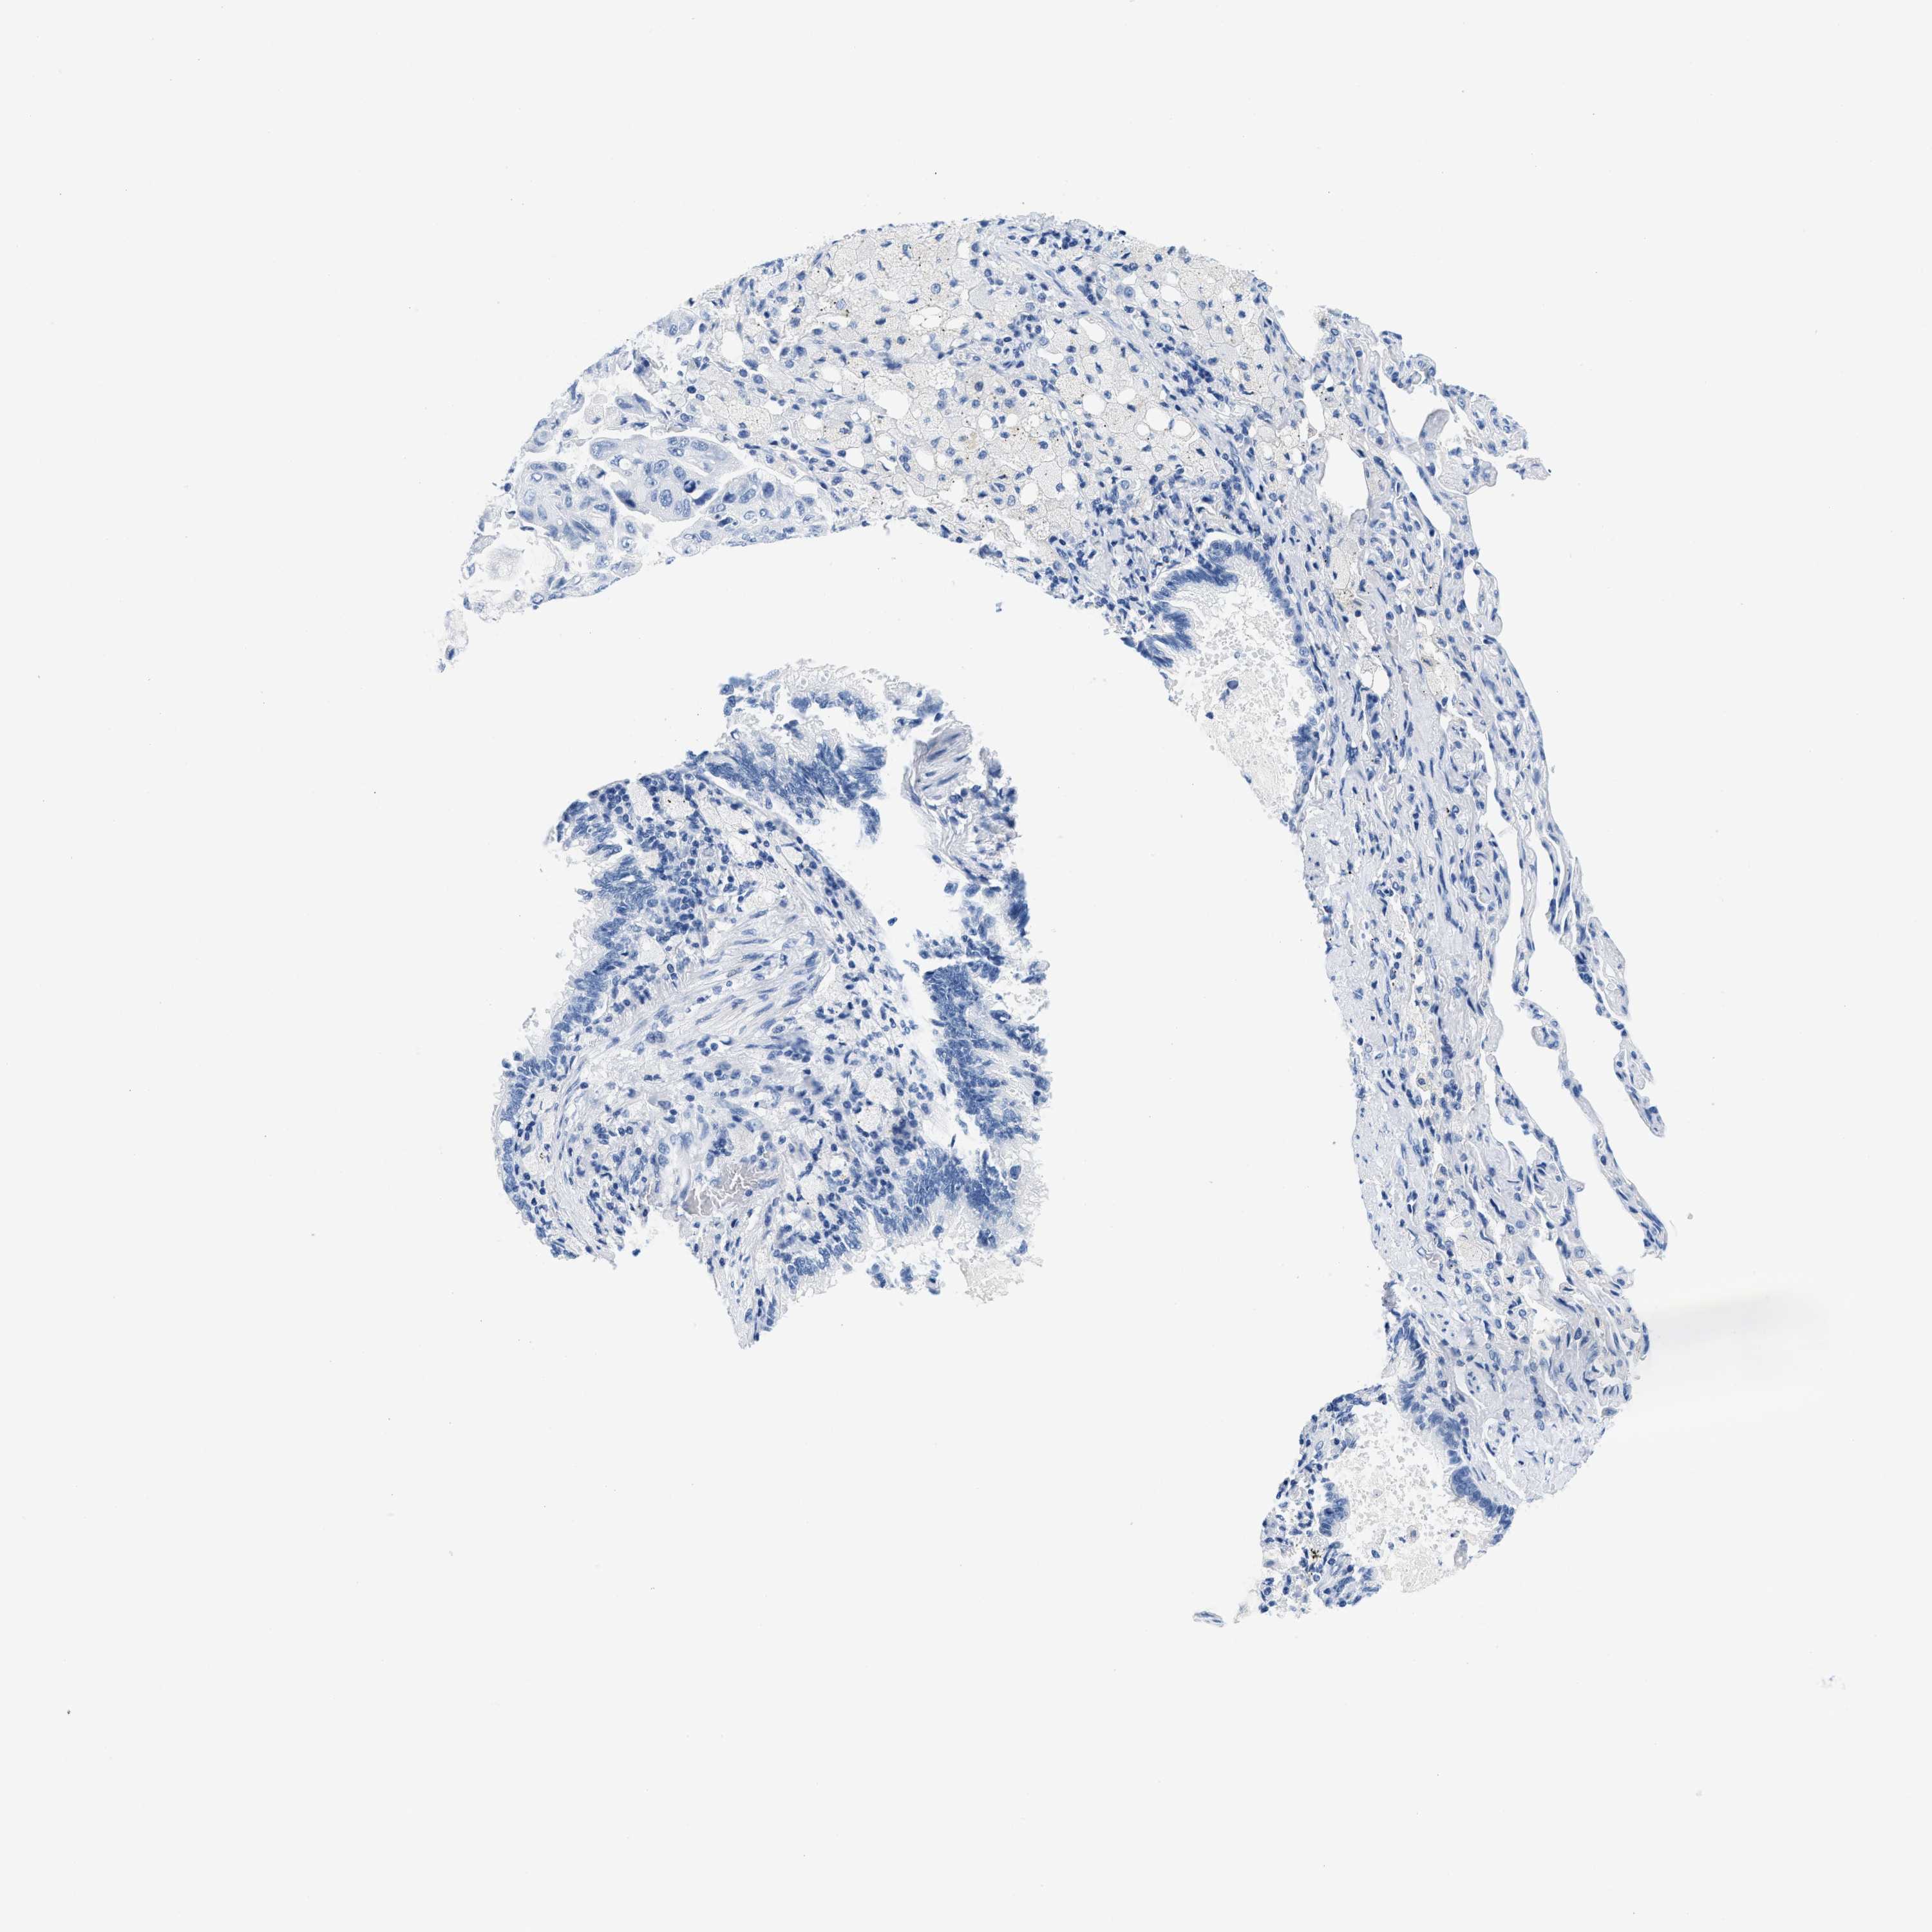

LUNG ADENOCARCINOMA (VALIDATION) - Interactive survival scatter ploti

The Survival Scatter plot shows the clinical status (i.e. dead or alive) for all individuals in the patient cohort, based on the same data that underlies the corresponding Kaplan-Meier plots. Patients that are alive at last time for follow-up are shown in blue and patients who have died during the study are shown in red.

The x-axis shows the expression levels (FPKM) of the investigated gene in the tumor tissue at the time of diagnosis. The y-axis shows the follow-up time after diagnosis (years). Both axes are complimented with kernel density curves demonstrating the data density over the axes. The top density plot shows the expression levels (FPKM) distribution among dead (red) and alive patients (blue). The right density plot shows the data density of the survived years of dead patients with high and low expression levels respectively, stratified using the cutoff indicated by the vertical dashed line through the Survival Scatter plot. This cutoff is automatically defined based on the FPKM cutoff that minimizes the p-score. The cutoff can be changed by dragging the vertical line or by entering a cutoff value in the square labeled "Current cut-off".

Under the Survival Scatter plot the p-score landscape (black curve; left axis) is shown together with dead median separation (red curve; right axis). Dead median separation is the difference in median mRNA expression between patients who have died with high and low expression, respectively. It is calculated as follows: median FPKM expression of dead patients with high expression - median FPKM expression of dead patients with low expression. This is intended to aid the user in visually exploring custom cutoffs and the associated p-scores and dead median separation.

Individual patient data is displayed and can be filtered by clicking on one or more of the category buttons on the top of the page. Categories describing expression level and patient information include: high, low, alive, dead, female, male and tumor stages. The scale of the x-axis can be toggled between linear and log-scale by clicking on the "x log" button. Mouse-over function shows TCGA ID, patient information and mRNA expression (FPKM) for each patient.

& Survival analysisi

Kaplan-Meier plots summarize results from analysis of correlation between mRNA expression level and patient survival. Patients were divided based on level of expression into one of the two groups "low" (under cut off) or "high" (over cut off). X-axis shows time for survival (years) and y-axis shows the probability of survival, where 1.0 corresponds to 100 percent.

GSN is not prognostic in Lung Adenocarcinoma (validation)

Best expression cut offi

Based on the FPKM value of each gene, patients were classified into two groups and association between prognosis (survival) and gene expression (FPKM) was examined. The best expression cut-off refers the FPKM value that yields maximal difference with regard to survival between the two groups at the lowest log-rank P-value. Best expression cut-off was selected based on survival analysis .

When clicking on this number, the vertical dashed line indicating cut-off, the interactive survival plot, and the Kaplan-Meier curve will be adjusted to show results based on the best expression cut-off.

: 120.31

P scorei

Log-rank P value for Kaplan-Meier plot showing results from analysis of correlation between mRNA expression level and patient survival.

N/A

TCGA RNA samplesi

RNA-seq data is reported as average FPKM (number Fragments Per Kilobase of exon per Million reads), generated by the The Cancer Genome Atlas (TCGA) .

Normal distribution across the dataset is visualized with box plots, shown as median and 25th and 75th percentiles. Points are displayed as outliers if they are above or below 1.5 times the interquartile range. FPKM values of the individual samples are presented next to the box plot.

Average pTPM 129.5

Number of samples 105